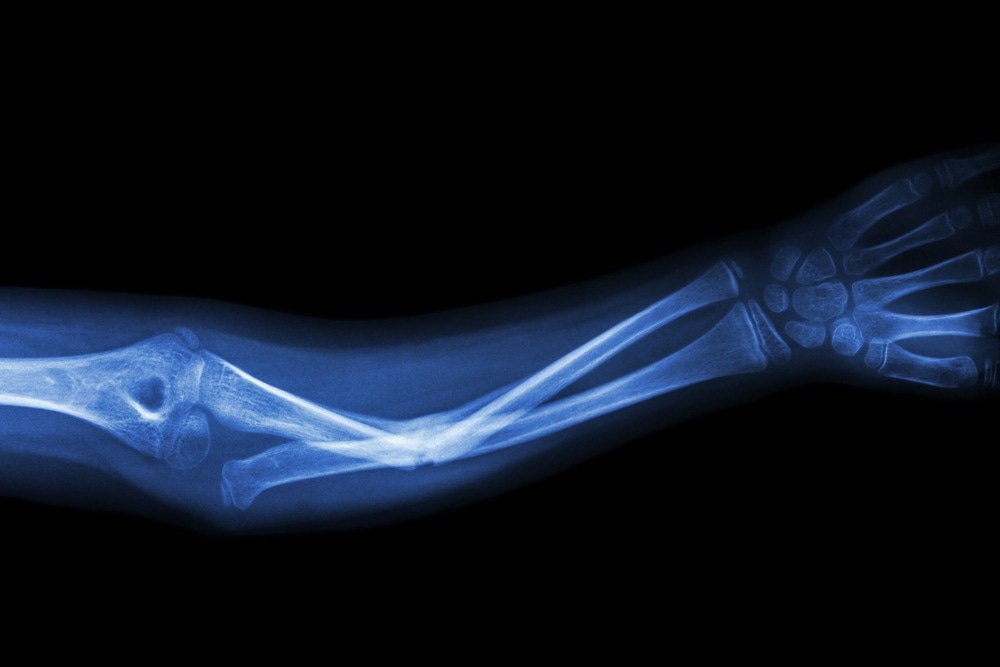

Affected people are at significant risk of suffering a bone fracture from even seemingly slight bumps and falls. In the general population, the frequency of ARO is 1 in 250 000, but it is much more common in certain geographical areas, such as the Middle East, Costa Rica, the Chuvash Republic of Russia, and the Province of Västerbotten in northern Sweden.

Typically, the distinctive findings in radiographic imaging are used to establish a diagnosis. Physical features and molecular genetic testing can also aid in diagnosis.